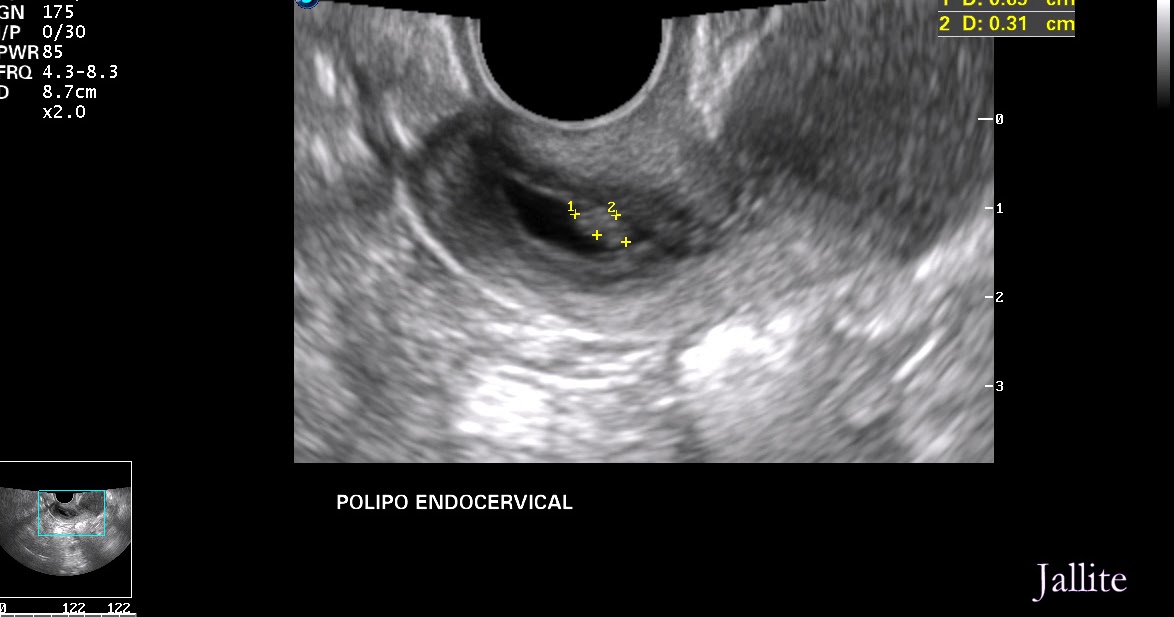

Doble Polipo Endometrial